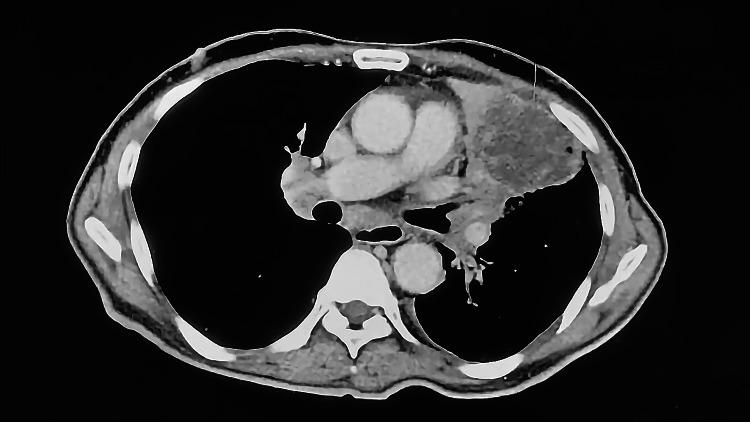

We report the first documented case series of two lung adenocarcinoma patients demonstrating Kirsten rat sarcoma viral oncogene homolog (KRAS) G12C mutations by reverse transcription-polymerase chain reaction techniques from Saudi Arabia. Both patients were males aged 64 and 76 years. The first had a heavy smoking history, while the second did not report any history of smoking. The tumor subtype was identified to be non-mucinous lung adenocarcinoma in both cases. The younger patient presented with generalized lymphadenopathy and a right-sided lung mass lesion, while the older patient exhibited stage III-A left lung adenocarcinoma that required rapid response. An initial examination of the first case showed a right-sided mediastinal shift, bilateral neck lymphadenopathy, and poorly differentiated neoplasm from a right supraclavicular core biopsy, leading to treatment with palliatives along with regular checkups. The second case was afebrile after being confirmed to be vitally stable and laboratory testing (Neutr 100). Further studies, specifically on large numbers of patients from the Arabian Gulf, are needed to confirm significant differences between the national and international populations. Additionally, future studies should investigate more differences in the differentiation of KRAS-mutant lung adenocarcinoma between patients from the Arabian Gulf and others.

我们报告了沙特阿拉伯首例通过逆转录-聚合酶链反应技术证实存在 Kirsten 大鼠肉瘤病毒癌基因同源物(KRAS)G12C 突变的两例肺腺癌患者的病例系列。两名患者均为男性,年龄分别为 64 岁和 76 岁。第一名患者有重度吸烟史,而第二名患者未报告任何吸烟史。两例患者的肿瘤亚型均被确定为非黏液性肺腺癌。较年轻的患者表现为全身淋巴结肿大和右侧肺部肿块病变,而较年长的患者表现为 III - A 期左肺腺癌,需要快速治疗。对第一例病例的初步检查显示右侧纵隔移位、双侧颈部淋巴结肿大,以及右锁骨上核心活检的低分化肿瘤,导致采用姑息治疗并定期检查。第二例病例在确认生命体征稳定且实验室检查(中性粒细胞 100)后无发热症状。需要进一步开展研究,特别是针对大量来自阿拉伯湾地区的患者,以确认本国人群与国际人群之间的显著差异。此外,未来的研究应调查阿拉伯湾地区患者与其他患者之间 KRAS 突变型肺腺癌分化方面的更多差异。